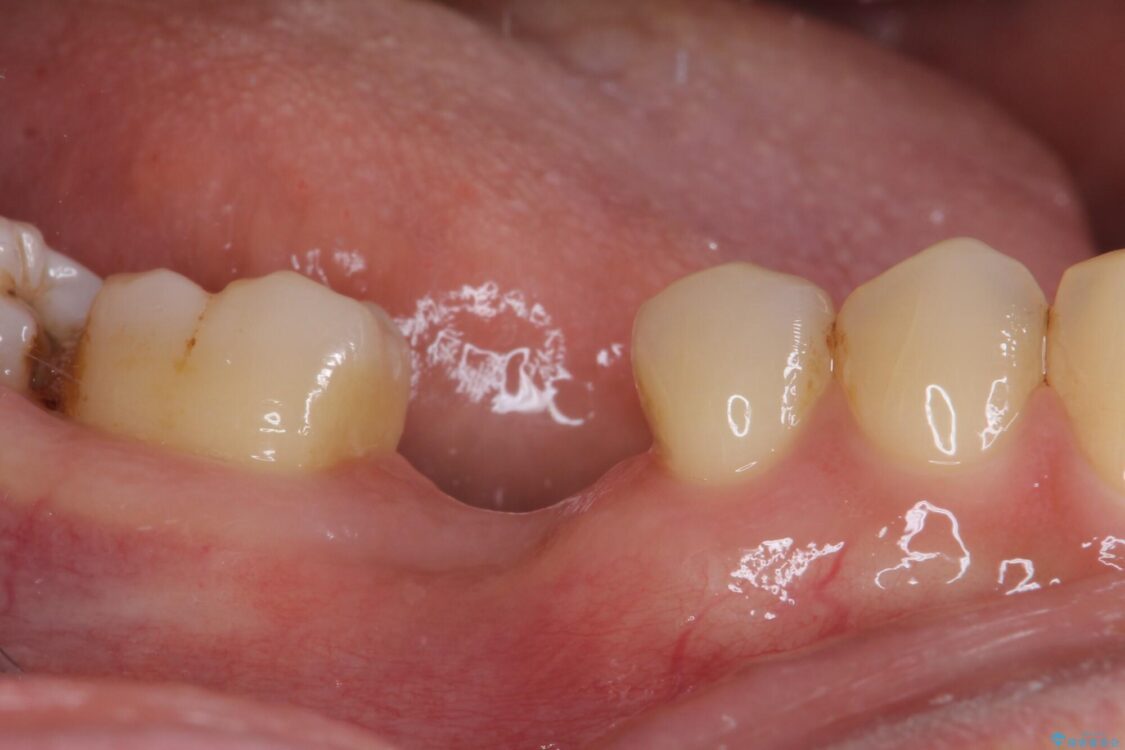

治療前

• 空いている時間を利用して通院 奥歯のインプラント治療 治療前画像